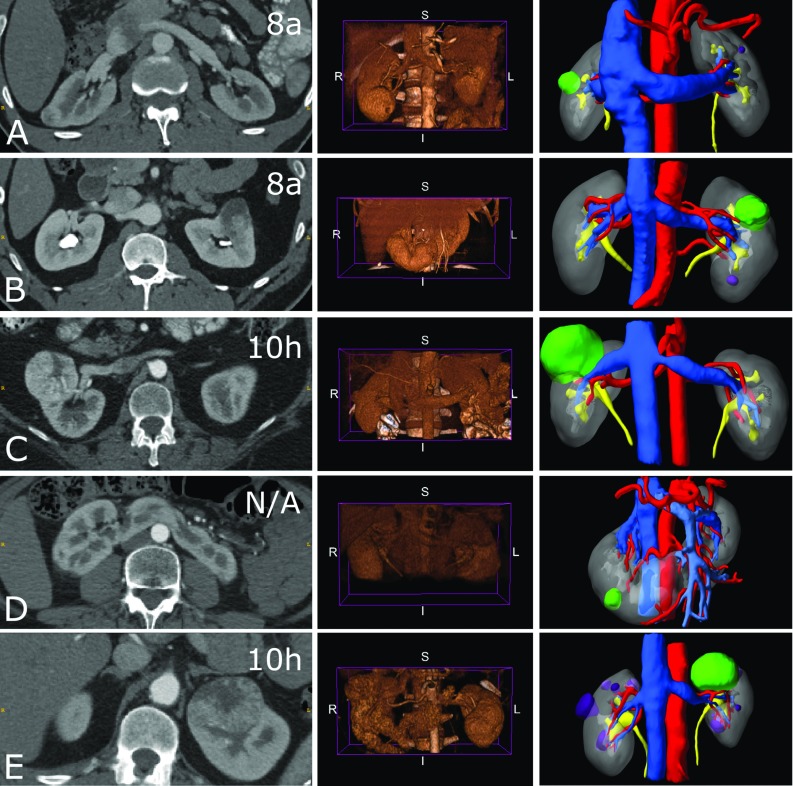

Fig. 1.

Representative imaging available for the 5 study cases a–e (rows) featuring: (left) arterial phase CT axial slice with the case RENAL score indicated in the top right corner. The horseshoe kidney case has not been given a RENAL score. (Middle) Arterial phase abdominal CT volume-rendered images (VRI) from an anterior viewpoint. (Right) A static screenshot of the generated, case-specific, interactive virtual 3D model which featured in the intervention arm of this study. The structure—colour keys are: artery—red; venous—dark blue; portal venous—light blue; tumour—green; cyst—purple; excretory—yellow; normal kidney—grey

A registry of patients who received clinically indicated and standard-of-care CT prior to surgery for renal masses between 2015 and 2017 was retrospectively reviewed by a urologist with expertise in kidney cancer surgery to identify 5 cases with RENAL nephrometry score greater than 7 (Table 1; Fig. 1, left). This study was approved by the local institutional review board at the Royal Free London NHS Foundation Trust, University College, London.

| A | Ant, Int, Lat | 21 | 8a (1, 3, 1, a, 3) | 9 (1, 3, 2, 1, 1, 1) | |

| B | Ant, Int, Med | 31 | 8a (1, 2, 3, a, 2) | 11 (1, 3, 2, 2, 1, 2) | Multiple renal arteries |

| C | Ant, Int, Hil | 54 | 10 h (2, 2, 3, h, 3) | 12 (2, 2, 2, 2, 2, 2) | |

| D | Pos, Low/Int, Lat | 18 | N.A. () | N.A. () | Horseshoe with portal vein |

| E | Ant, Upp/Int, Med/Hilar | 57 | 10 h (2, 2, 3, h, 3) | 12 (2, 2, 2, 2, 2, 2) |

Nephrectomy scores are followed by their component-wise breakdown. Letters A–E correspond to the cases A–E illustrated in Fig. 1

Ant anterior, Pos posterior, Upp upper pole, Int interpole, Low lower pole, Lat lateral, Med medial, Hil hilar